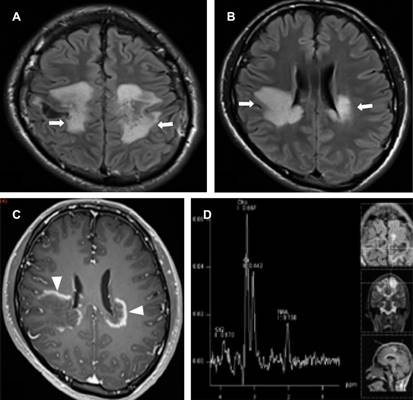

Masculino de 17 años con dos semanas de febrícula, cefalea, ataxia, disminución de agudeza visual de predominio derecho, temblor, fuerza disminuida en extremidades. Laboratoriales: leucocitos 10,100/mm3 con 75%N, proteína C reactiva (PCR) 41.2 mg/L, ELISA VIH negativo, tóxicos en orina negativos. Punción lumbar: leucocitos 70/μL (92% mononucleares), glucosa 68 mg/dL, sugerentes de EMDA, se realizó resonancia de ingreso (Figura 1); se descartó EM por negatividad de bandas oligoclonales IgG específicas, con positividad para anticuerpos anti-MOG mediante EBC. El tratamiento agudo se realizó con metilprednisolona intravenosa a dosis altas con discreta mejoría, en resonancia control presentó compromiso de médula espinal, así como de nervios ópticos (Figura 2); se adicionaron inmunoglobulinas, ocho meses después presentó mejoría sintomática. En resonancia de seguimiento para valoración de tratamiento con disminución de lesiones sin realce de las mismas (Figura 3).

Figura 1: Resonancia magnética cerebral. A y B) Axial FLAIR. Hiperintensidades en la sustancia blanca en centros semiovales, frontoparietales y periventriculares (flechas). C) T1 con gadolinio con reforzamiento periférico de las lesiones (cabezas de flechas). D) Espectroscopia: picos de colina con notable disminución del valor del N-acetilaspartato, lípidos y lactato sugerentes de proceso inflamatorio.